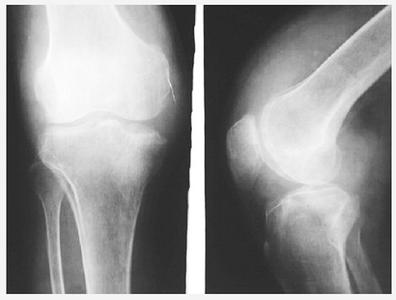

滑膜炎需要做哪些预防措施

滑膜炎给我们的身体带来的危害是非常大的,严重的还会时节关节知觉功能,所以我们在平时一定要注意预防滑膜炎的发生,在平时一定要坚持锻炼,当然这里所说的锻炼不是说的剧烈运动。下面大家就一起来看看贵阳治疗滑膜炎医院专家的详细讲解吧。